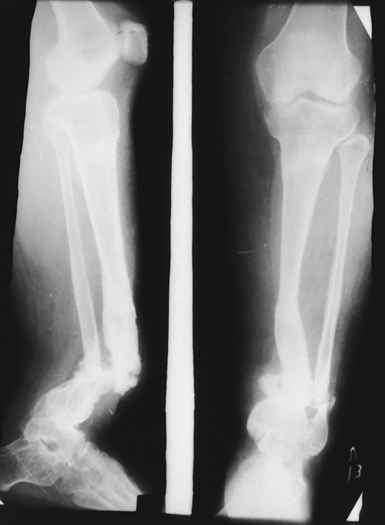

Случай, который я представляю, был сделан мной около 20 лет назад в Кургане.

Женщина 28 лет, пошедшая 13 предыдущих оперативных вмешательств по-поводу ВПБ имела 9 см. укорочения.

На первом этапе аппаратом Илизарова закрыто устранена деформация голени.

На втором этапе произведёно освежение краёв костных фрагментов б/б и м/б костей с приданием проксимальному фрагменту б/б кости впалой, а дистальному выпуклой формы, открытие канала проксимального фрагмента и погружной остеосинтез, а также остеотомия б/б кости в в/3 и м/б кости на границе с/3 и н/3 голени. Больной проводился одновременный бифокальный компрессионно-дистракционный остеосинтез. Достигнуто 11 см. удлинение и сращение ВПГ.

Срок лечения 11 месяцев. Наблюдение 2 года.